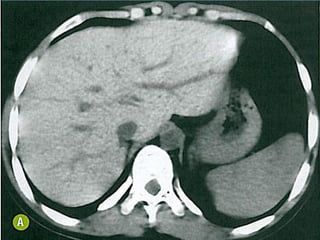

ACHADOS DE IMAGEM

• TC:

– Muito limitada;

• RM:

– Atrofia cerebral e cerebelar;

– Perda da interface SB-SC;

– Hiperssinal T2/FLAIR simétrico em pedúnculos cerebelares

médio e braço posterior da cápsula interna;

– Afilamento do corpo caloso;

– Hiperssinal de SB também pode ser visto;

Hipossinal em T2 em núcleos denteados cerebelares,

tálamo, SN e núcleos rubros indica deposição de Fe;